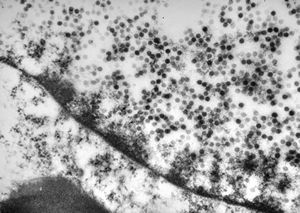

rotavirus isolated from intestine